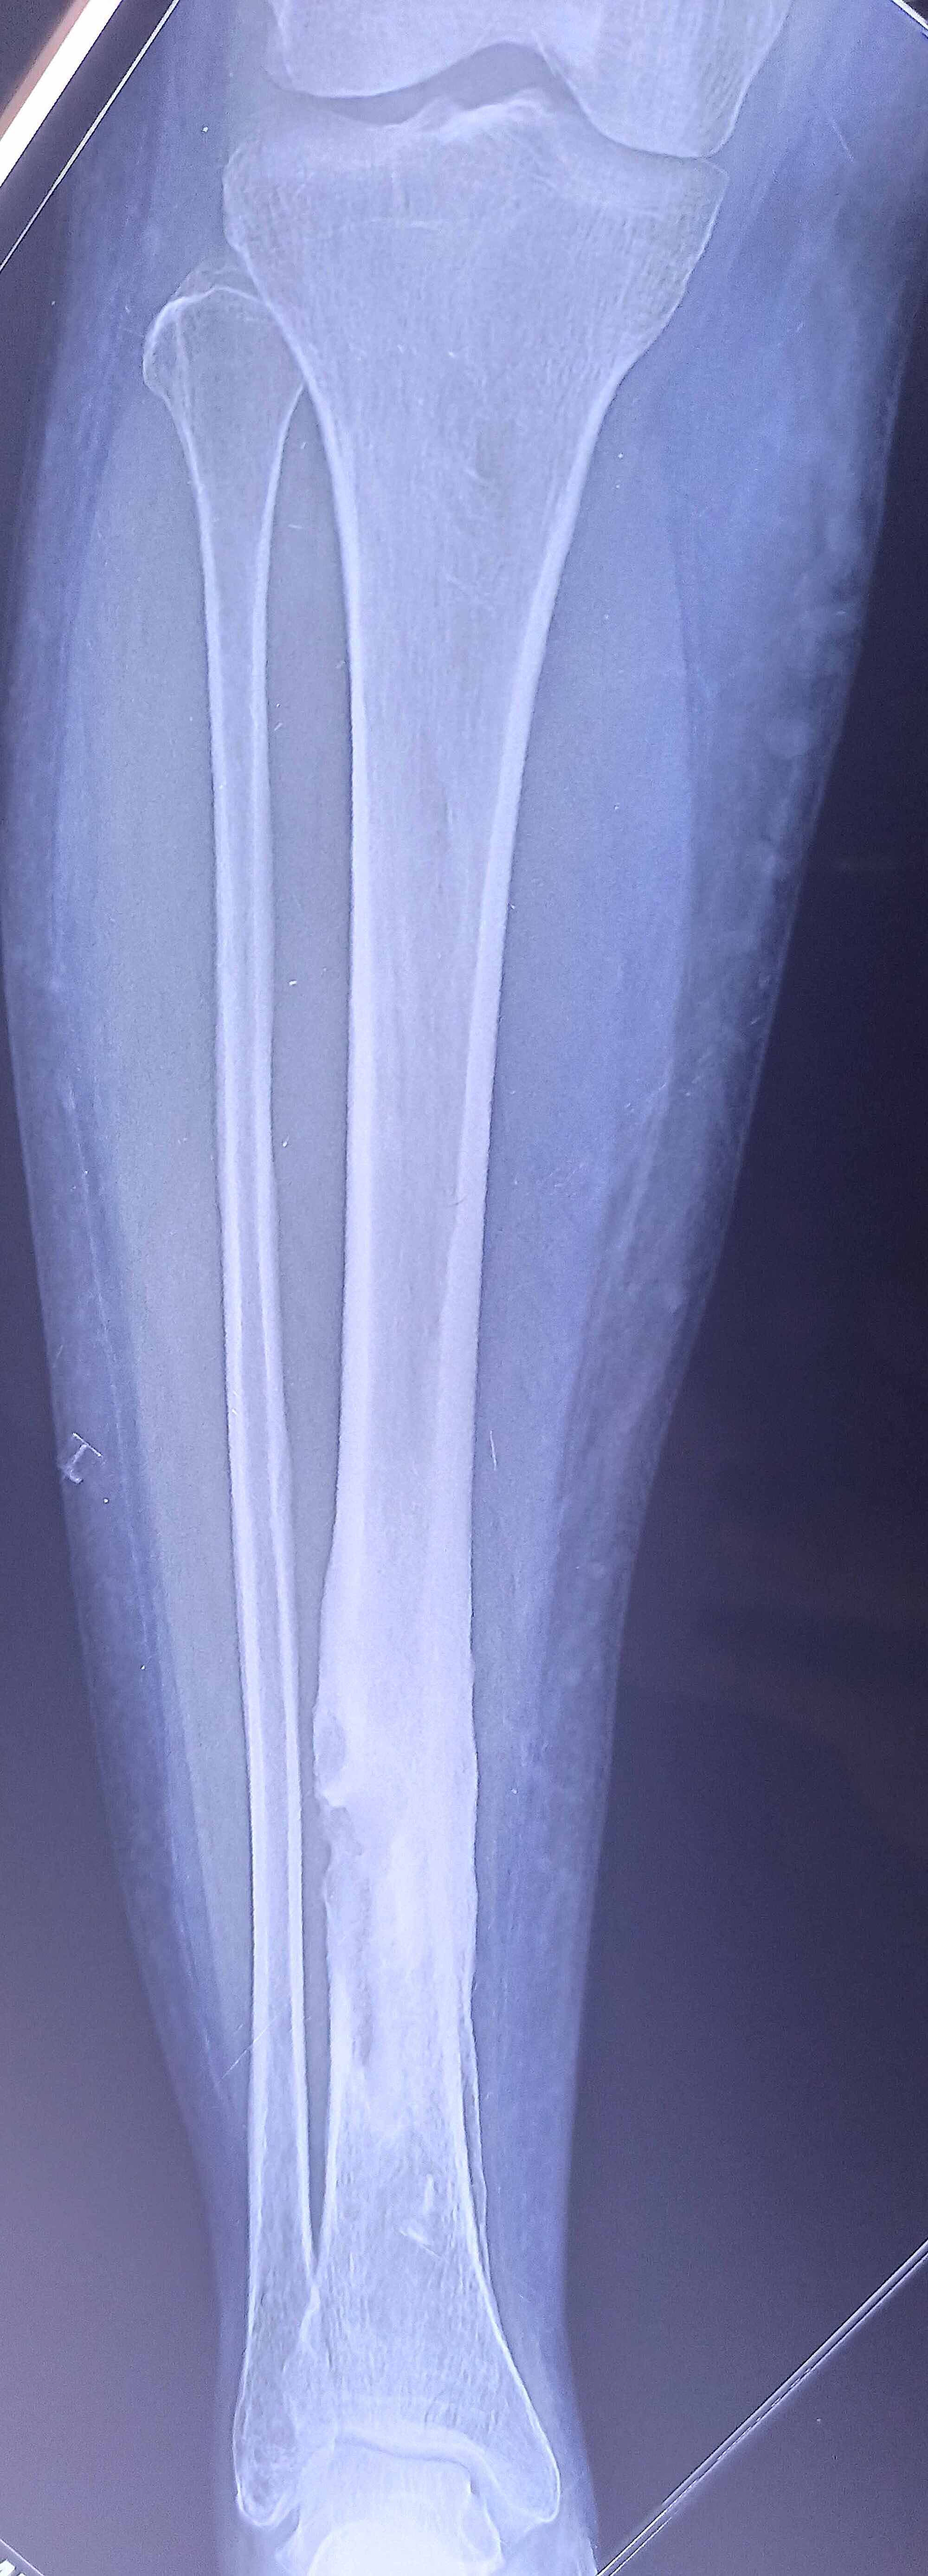

Figure 1 from Salmonella Osteomyelitis of the Distal Tibia in a Healthy Salmonella Osteomyelitis Symptoms More than a half patients suffer salmonella. Salmonella osteomyelitis is often overlooked, causing misdiagnoses and delays. Enteric fever, acute gastroenteritis, bacteraemia with or without. Salmonella species are a common cause of osteomyelitis in developing countries and among patients with sickle cell disease. 10 infections due to kingella. Bone infection is called osteomyelitis. Salmonella infection can cause four predominant clinical syndromes:. Salmonella Osteomyelitis Symptoms.

JBJI Salmonella osteomyelitis of the distal radius in a healthy Salmonella Osteomyelitis Symptoms Enteric fever, acute gastroenteritis, bacteraemia with or without. More than a half patients suffer salmonella. It is an acute or chronic inflammatory process involving the bone and its structures secondary to infection with. Bone infection is called osteomyelitis. Salmonella osteomyelitis is often overlooked, causing misdiagnoses and delays. Salmonella infection can cause four predominant clinical syndromes: Salmonella species are a common. Salmonella Osteomyelitis Symptoms.